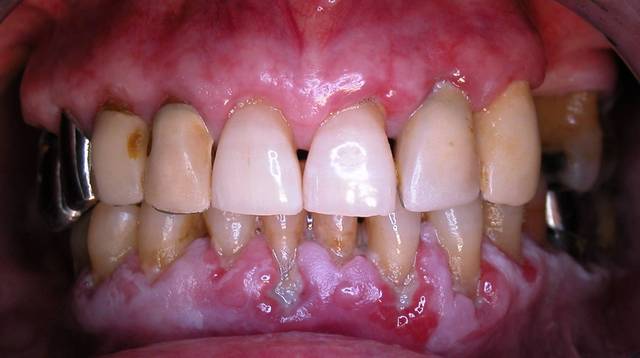

je vois une patiente en consultation, aujourd'hui. Elle se plaint de problèmes de gencives qui saignent... Quand vous verrez les photos vous comprendrez pourquoi.

Le problème, n'est pas la parodontite, mais des lésions blanches, situées surtout à la mandibule. La patiente ne fume pas et ces lésions ne partent pas au grattage.

Alors lichen plan ou kératose?

c'est adhérent mais cela un toucher granité.

lichen plan presque sur ......

il me semble que le pemphigus et l'erythème polymorphe sont des maladies bulleuses avec des signes généraux souvent associés et des lésions des joues et des lèvres à un stade développé .......pour cette patiente dont les lésions sont évoluées tout semble localisé sur la gencive .......pour avoir vu beaucoup de lichen plan j'ai tendance à penser à cela avec une leucoplasie associée par endroit

Tout dépend de l'HDM (histoire de la maladie) pour l'extension, sinon effectivement le diagnostic macroscopique est complexe, mais oon retrouve un aspect placardant en mosaïque, je serai curieux d'avoir le résultat de la biopsie, je m'avoue un peu sec devant la photo, et incertain

D'après un confrère spécialisé en pathologie buccale, c'est donc un lichen. Merci les gars.